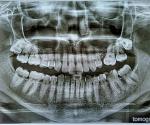

"В третий раз натираю десну пищей, в том месте где должен быть нижний зуб мудрости, у меня их нет и никогда не будет. " - Это подтвердили рентгенологическим обследованием? Пришлите рентгенограмму.

Вот ортопанорама.

Верхний один зуб мудрости уже удален. И остальные зубы подлечены.

Первый раз воспалился карман над шестеркой, он был не до конца прорезанный в 34 года, да и один молочный зуб до сих пор есть, врач сказала. Карман срезали, но потом опять воспалилась десна. Там все разы как маленький волдырь. Второй раз полоскание и метрогил помогли.